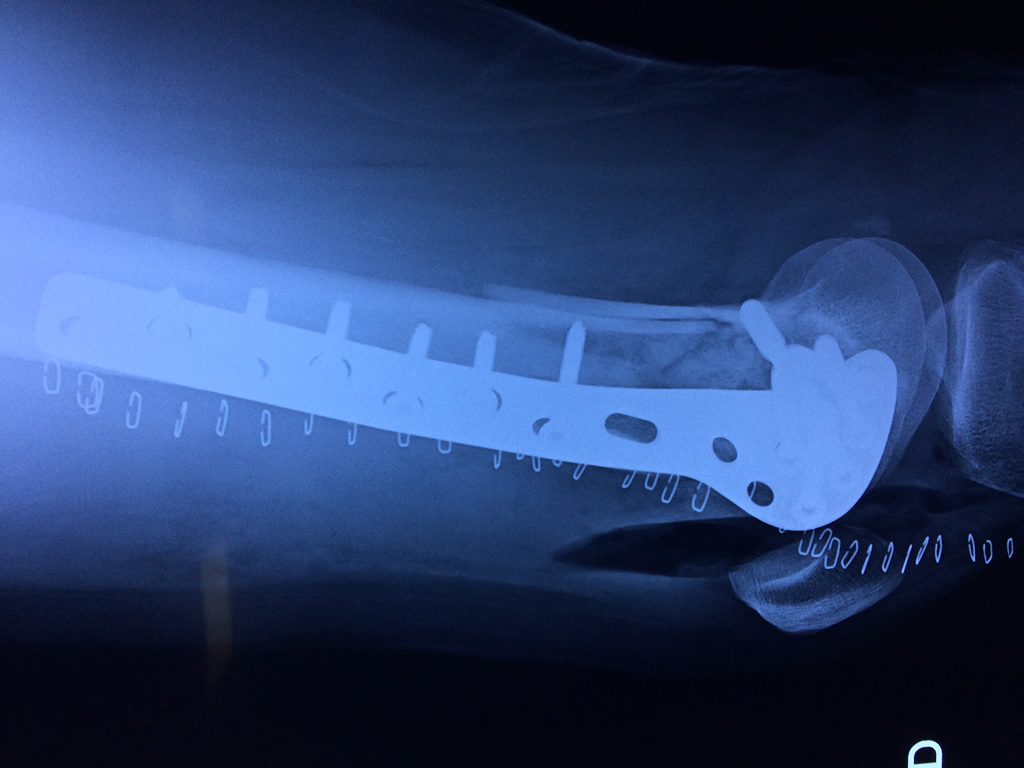

Cirugías de Codo - Fémur

El fémur es el hueso del muslo, el segundo segmento del miembro inferior. Es el hueso más largo, fuerte y voluminoso del cuerpo humano.